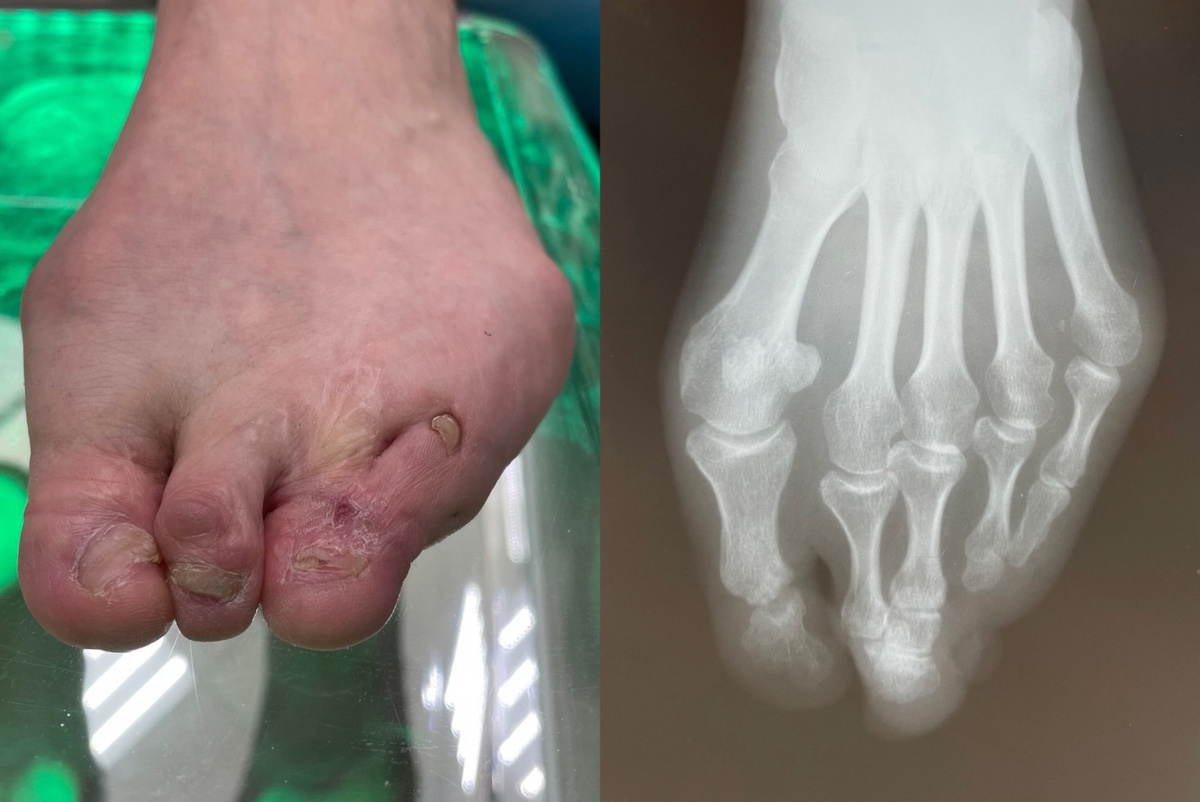

Синдактилия – это интересный и в то же время сложный медицинский термин, обозначающий врожденный или приобретенный порок развития конечностей. При этом два или более пальцев на кистях или стопах могут срастаться как полностью, так и частично. В этом статье мы подробнее рассмотрим причины, виды и способы лечения синдактилии.

Синдактилия классифицируется по нескольким критериям:

➖ Тип соединения: Соединение пальцев может происходить в виде тонкой перепонки – кожной перемычки, которая может охватывать всю длину пальцев. Также возможно сращение, при котором вовлечены мягкие ткани, кровеносные и лимфатические сосуды, а также нервные окончания.

➖ Длина сращивания: Сращение может происходить по всей длине пальцев или затрагивать одну или две фаланги, включая соединительные или костные ткани.

➖ Кожный мешочек: В некоторых случаях несколько пальцев могут оказаться в одном «кожном мешочке», при этом все фаланги развиты, и даже имеются ногти.

Синдактилия нередко сопутствует другим патологиям, таким как полифалангия или полидактилия, что усложняет процесс диагностики и лечения.